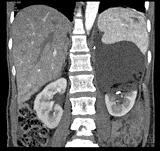

问题 男,28岁,交通事故受伤,查体:有休克症状,请结合CT图像,选择最可能诊断 ( )

选项 A、脾破裂 B、腹膜后出血 C、左肾裂伤并大血肿形成 D、左肾包膜下出血 E、左肾挫伤

答案 C